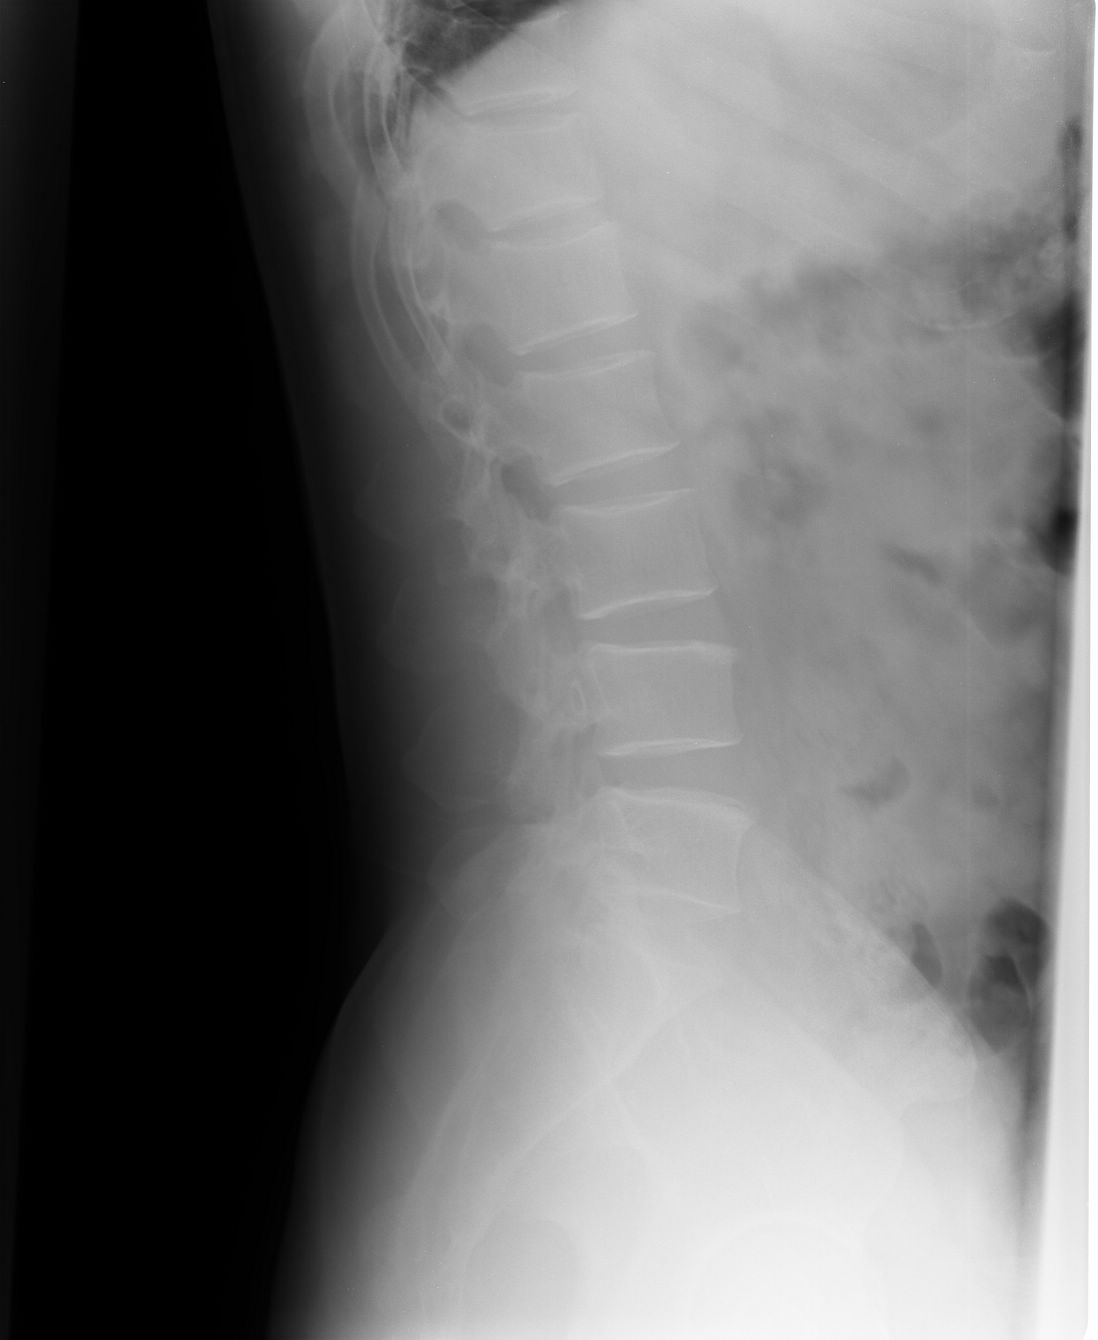

以下是引用liaoqiang在2008-9-2 15:27:00的发言:[br]耻骨联合分离。当心有尿道、膀胱损伤可能。

以下是引用杀毒软件在2008-9-2 17:20:00的发言:[br]支持 -------耻骨联合分离,骶骨近左侧耳状面骨折.

以下是引用随光逐影在2008-9-2 16:56:00的发言:[br]支持 耻骨联合分离,骶骨近左侧耳状面骨折并左侧骶髂关节分离。

以下是引用dyqct在2008-9-2 15:42:00的发言:[br]耻骨联合分离,左侧骶髂关节半脱位。建议ct进一步检查。